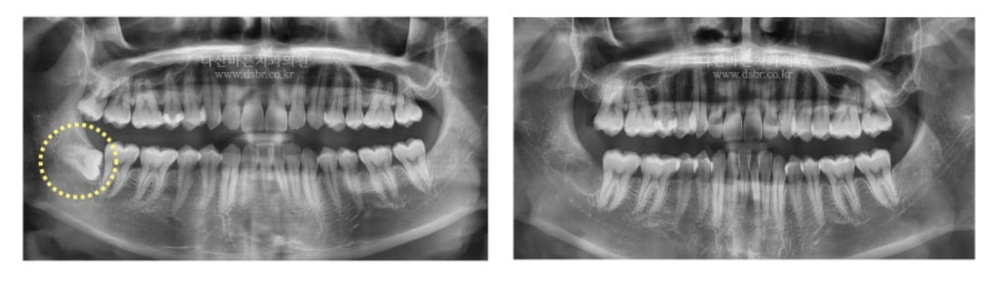

Đây là trường hợp răng khôn nằm ngang và bị ảnh hưởng sâu hơn một chút.

Đây là trường hợp cần phải lấy xương cầu kỳ hơn vì răng khôn đã mọc hoàn toàn vào xương nướu.

Ngoài ra, như trong ảnh CT bên dưới, răng khôn và dây thần kinh gần như tiếp xúc với nhau

nên đây là trường hợp cần thực hiện một cách tiếp cận tinh tế và cẩn thận hơn trong quá trình

phân chia răng để nhổ răng. Tuy mất nhiều thời gian hơn những trường hợp trước

một chút nhưng đây là trường hợp răng được nhổ thành công mà không có dấu hiệu tổn thương thần kinh.

Dây thần kinh gần răng khôn.